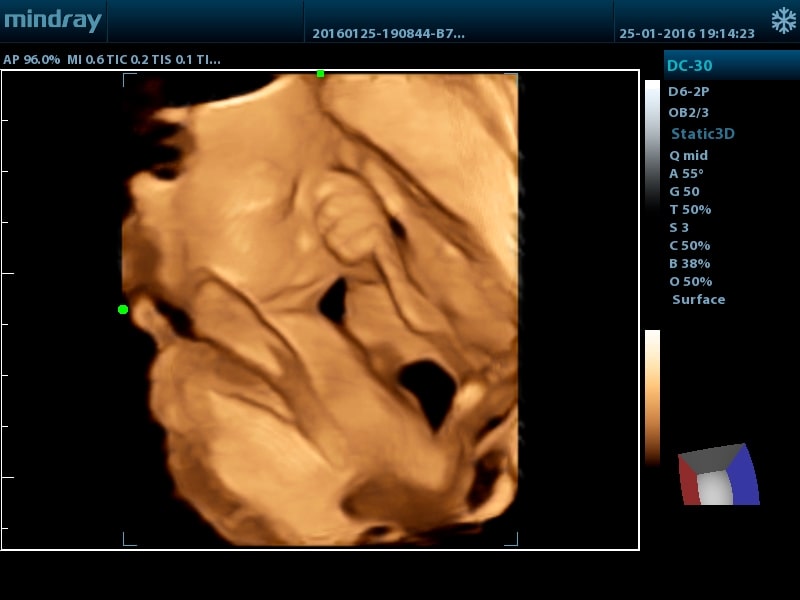

- Smart 3D™ - трехмерная реконструкция методом "свободной руки" (FreeHand 3D)

- Smart NT Программное обеспечение для автоматического измерения толщины воротникового пространства у плода

- Smart OB™ Программное обеспечение для автоматического измерения основных параметров биометрии плода в акушерстве